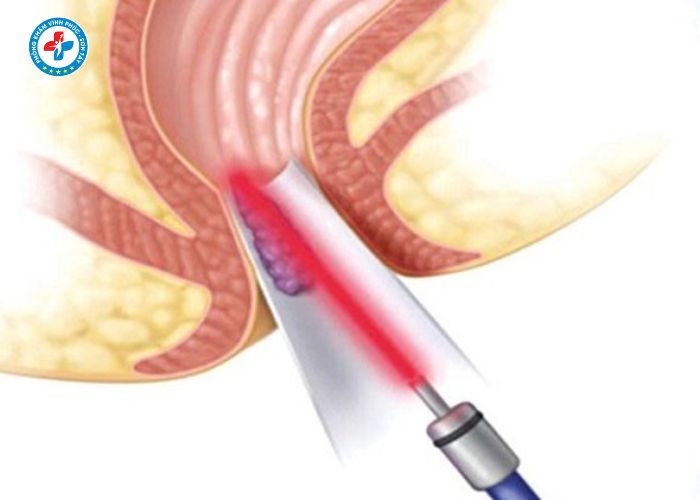

Tiêm trĩ (tiêm xơ búi trĩ) là phương pháp sử dụng thuốc chuyên dụng để tiêm trực tiếp vào búi trĩ nhằm làm xơ hóa mạch máu, giảm kích thước và làm búi trĩ teo dần.

3. Tiêm xơ búi trĩ

- Tiêm thuốc vào chân búi trĩ

- Thuốc làm co mạch và xơ hóa búi trĩ